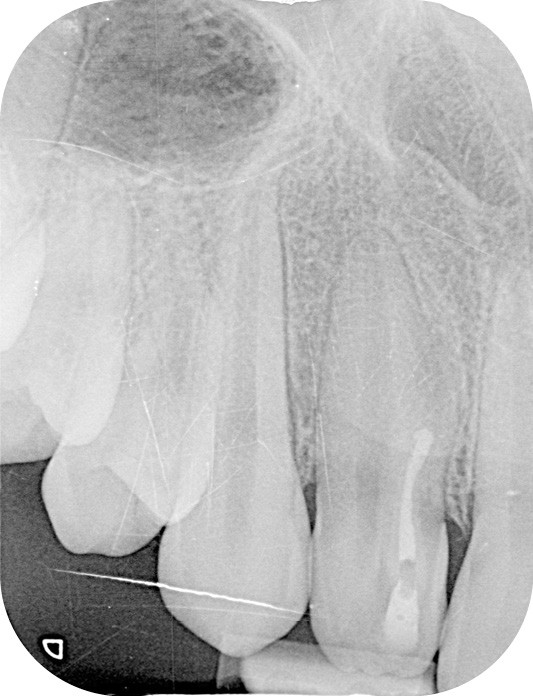

La patiente, âgée de 12 ans, s’est présentée à ma consultation avec une demande du chirurgien de réaliser le traitement endodontique de la 12 avant le curetage sous anesthésie générale. La radiographie périapicale préopératoire a mis en évidence une anatomie complexe. Les tests préopératoires ont montré un sondage parodontal sain, une percussion positive et un test au froid positif. La patiente présentait également une fistule vestibulaire active. Le Cone Beam a mis en évidence la présence d’une dens in dente et d’une lésion imposante ainsi qu’une palatoversion importante de la racine de la 12. La lésion est-elle responsable de ce mouvement dentaire ? (fig. 1, 2 et 3).

Le contrôle clinique à un mois m’a permis d’apprécier une cicatrisation complète de la fistule, augurant une future cicatrisation osseuse (fig. 7). Cette cicatrisation a pu être objectivée radiographiquement lors du contrôle à 6 mois (fig. 8), du contrôle à 1 an (fig. 9) et sur le Cone Beam à 1 an (fig. 10).